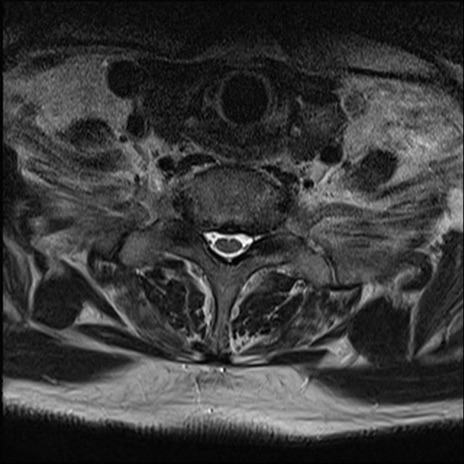

【整形】TIPS症例7 頚椎MRI T2WI(横断像)

頚椎MRI

矢状断像と横断像